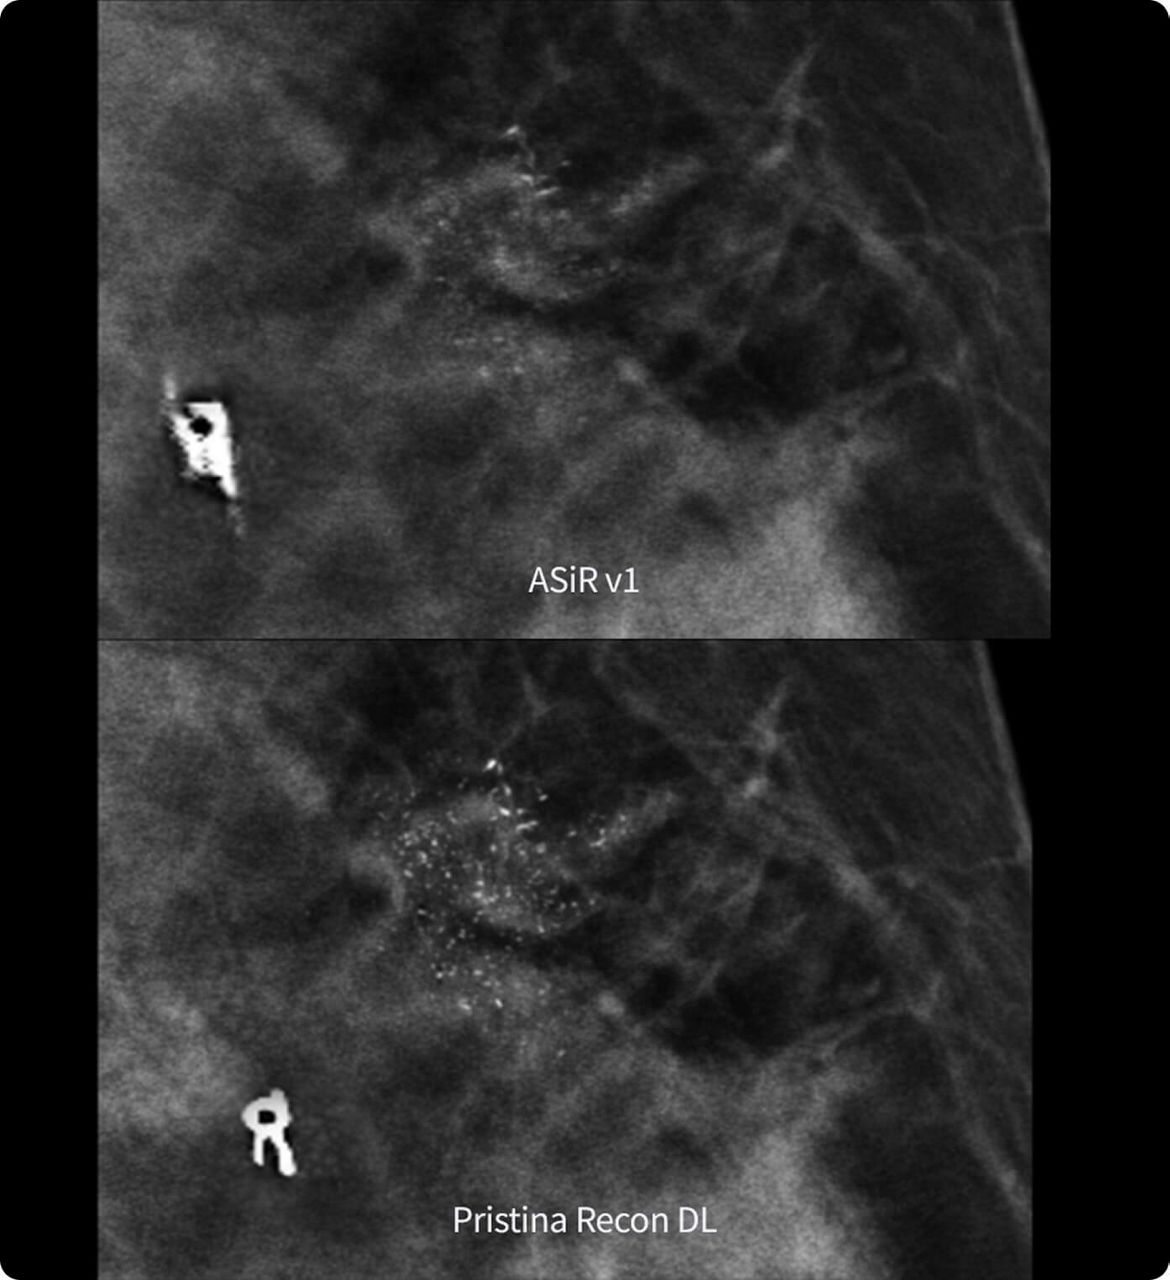

Enhanced definition

Optimized contrast

Pristina Recon DL also features an improved tissue compensation algorithm designed to homogenize image brightness across the entire breast, from the pectoral muscle to the skin line. This helps eliminate the need for manual windowing and minimizes the thick skin artifacts, revealing a clean and well-defined skin line.

1. Preference study performed on 140 study cases with 8 MQSA-approved radiologists, trained on clinical image quality by ACR, comparing Pristina Recon DL to ASiR v1.

2. Reader performance evaluation on 19 680 reads with 8 readers using modeled clinical data comparing Pristina Recon DL and ASiR v1.